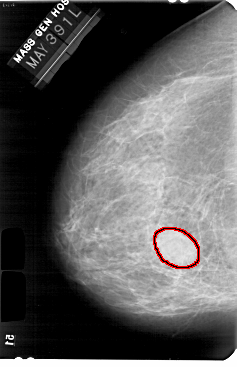

A_1733_1.LEFT_CC

LEFT_CC LINES 5491 PIXELS_PER_LINE 3541 BITS_PER_PIXEL 12 RESOLUTION 43.5 OVERLAY

FILE: A_1733_1.LEFT_CC.OVERLAY

TOTAL_ABNORMALITIES 1

ABNORMALITY 1

LESION_TYPE MASS SHAPE LOBULATED MARGINS CIRCUMSCRIBED

ASSESSMENT 3

SUBTLETY 5

PATHOLOGY BENIGN

TOTAL_OUTLINES 1

BOUNDARY